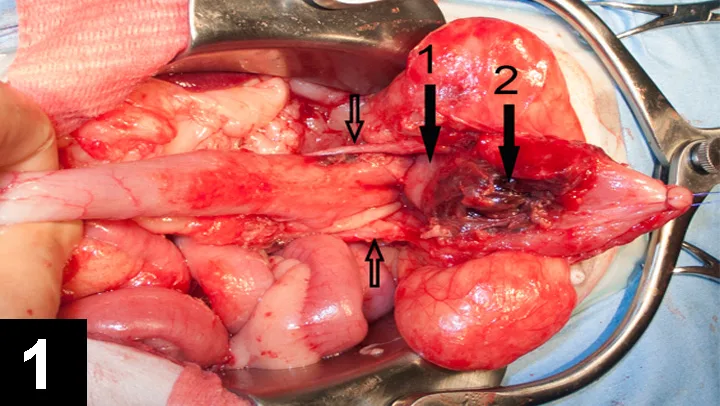

For various reasons, probably including time constraints, OVH is often performed through an as-small-as-possible abdominal incision, whether a ventral midline or flank approach is used, that is located to attempt to allow visualization of both the ovaries and the cervix but is optimal for neither; this can result in relatively poor exposure. Significant traction is required to reach the uterine body, and excessive traction on the uterus has been associated with rupture of uterine vessels and hemorrhage16 and is unnecessarily traumatic. Often, the cervix cannot be reached and identified when using a small incision approach; the uterus is, therefore, ligated and sectioned either without precise visual control, which exposes the patient to complications (Figure 1), or too cranially, leaving a significant portion or all of the uterine body (Figure 2). Such an incomplete resection is unlikely to cause problems but somewhat negates the putative advantages of OVH. This difficulty in reaching the cervix may be even greater with a flank approach,10,17 requiring considerable retraction of the abdominal wound, which may contribute to more postoperative pain than would a ventral midline approach.18

Figure 2

Intraoperative view of a uterine stump reveals that the cervix (yellow  arrow) and most of the uterine body (white arrow) remain in place in this dog.